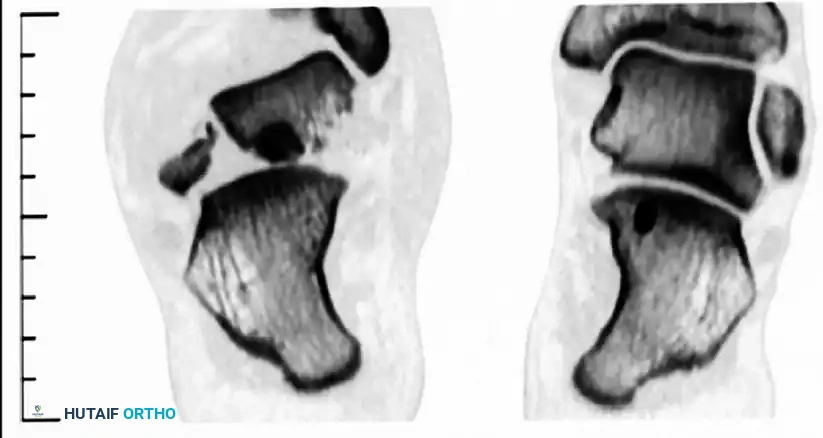

Computed Tomography (CT)

A fine-cut CT scan with sagittal and coronal reconstructions is the gold standard for preoperative planning. It delineates fracture lines, identifies intra-articular step-offs, and reveals concomitant injuries such as lateral process fractures or subtalar debris.